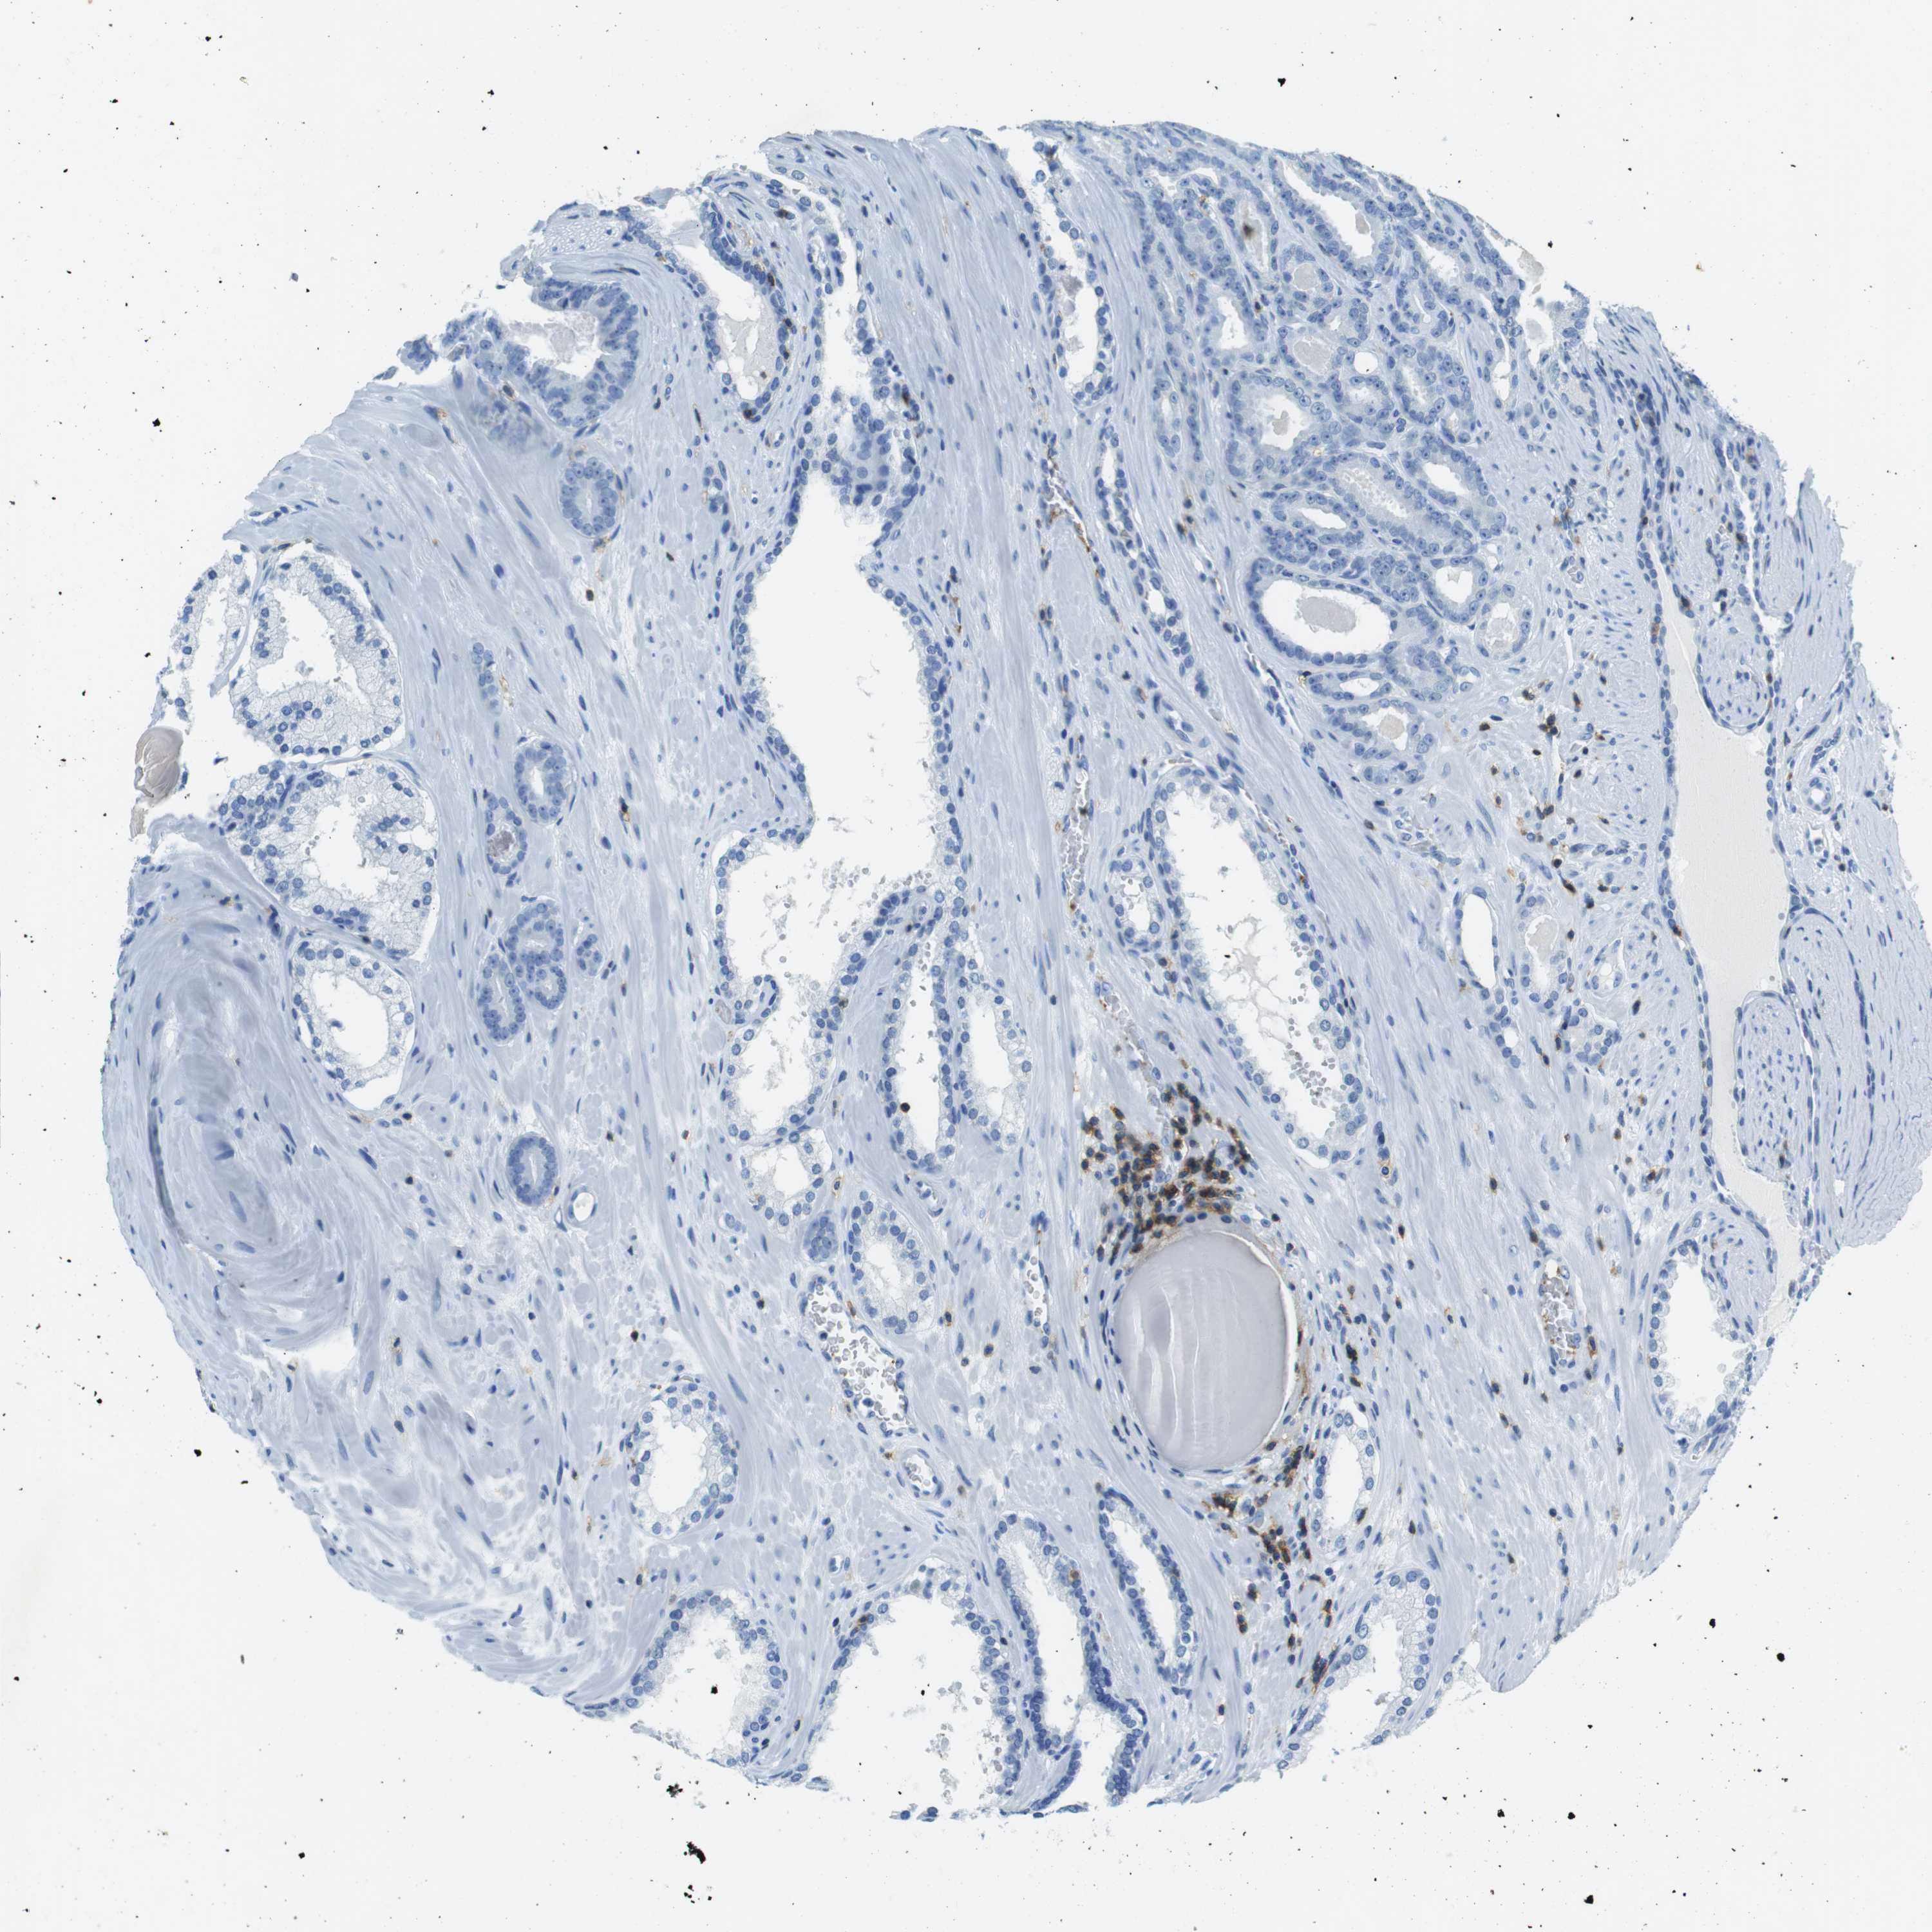

PROSTATE CANCER - Protein expressioni

A mouse-over function shows sample information and annotation data. Click on an image to view it in a full screen mode. Samples can be filtered based on level of antibody staining by selecting one or several of the following categories: high, medium, low and not detected. The assay and annotation is described here.

Note that samples used for immunohistochemistry by the Human Protein Atlas do not correspond to samples in the TCGA dataset.

Antibody stainingi

Antibody staining in the annotated cell types in the current human tissue is reported as not detected, low, medium, or high, based on conventional immunohistochemistry profiling in selected tissues. This score is based on the combination of the staining intensity and fraction of stained cells.

Each image is clickable and will lead to virtual microscopy that enables deeper exploration of all samples and also displays staining intensity scores, fraction scores and subcellular localization as well as patient and tissue information for each sample.

Antibody HPA011157

Antibody CAB002223

Antibody CAB012978

Antibody CAB079960

Staining

High

Medium

Low

Not detected

Intensity

Strong

Moderate

Weak

Negative

Quantity

>75%

75%-25%

<25%

None

Location

Nuclear

Cytoplasmic/membranous

Cytoplasmic/membranous,nuclear

Adenocarcinoma, Low grade

Adenocarcinoma, High grade

Adenocarcinoma, Medium grade

Adenocarcinoma, NOS